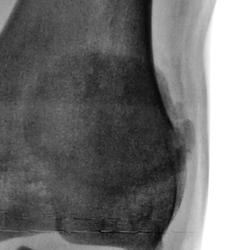

Направлен был традиционно из военкомата для рентгенографии стоп и позвоночника. Но лаборант заметил, что "клиент" полностью, в положении лёжа, ноги в коленных суставах не разгибает. Решили дополнительно "снять" коленные суставы...

Дисплазия это...

МРТ полностью подверждает дисплазию

Эпифизарная дисплазия.

Оказалось, что и ранее снимки производились.